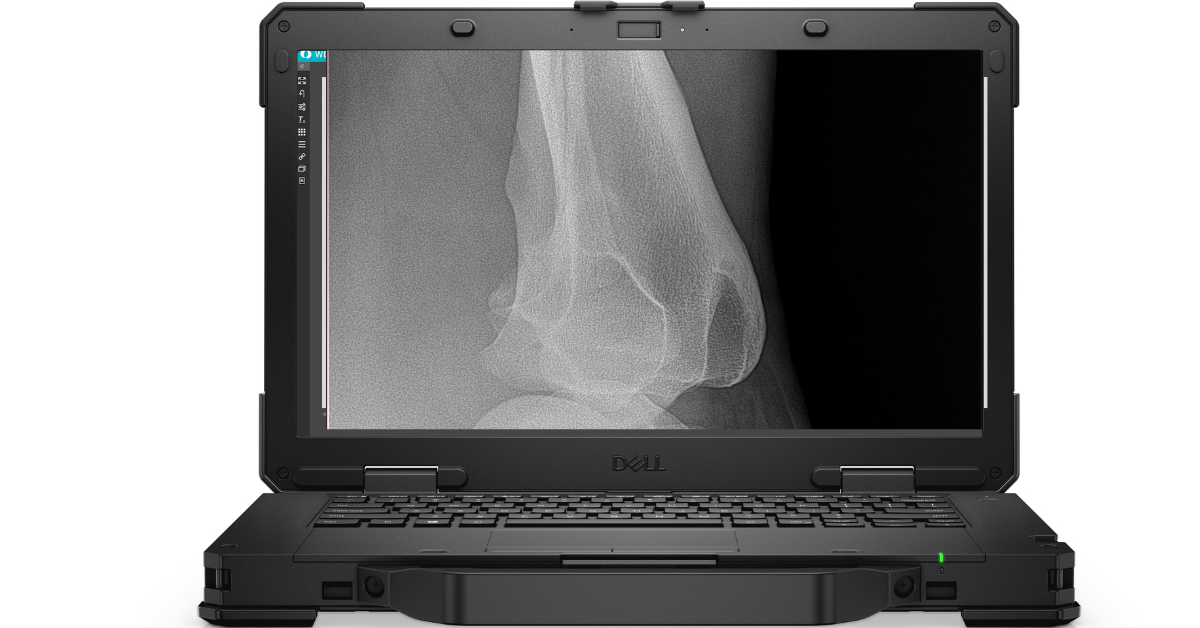

Rugged Computer and case

Latitude 5430 Rugged Laptop

14" Non-touch Display,

Intel i% processor,

16GB RAM

512GB

SSD Memory

3-year warranty

Pelican case sized for detector and laptop